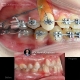

درمان ارتودنسی بدون کشیدن دندان در کیس همراه با دندان نیش نیمه نهفته و شیفت میدلاین دندانی.

Non extraction orthodontic treatment done for a case with semi_impacted canine and huge midline shift.